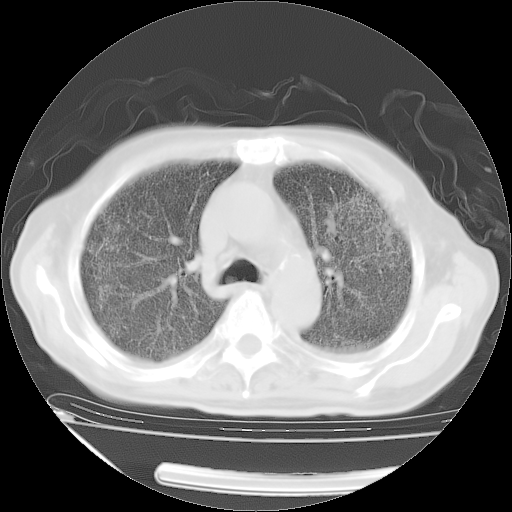

甲强龙80mg/日+抗结核治疗(异烟肼+利福霉素+乙胺丁醇)10天。复查肺部CT。

治疗10天肺部CT

仔细阅读病史资料和CT,我觉得两肺粟粒结核要高度怀疑。

今天带四次肺CT片到市医院,影像科4~5个主任都认为不考虑粟粒性肺结核。主要理由是在3月19日、4月2日、4月27日的CT片没有见到确切异常(肺结核)影像。影像科主任们建议找呼吸内科主任,呼吸内科主任认为首先考虑粟粒性肺结核。